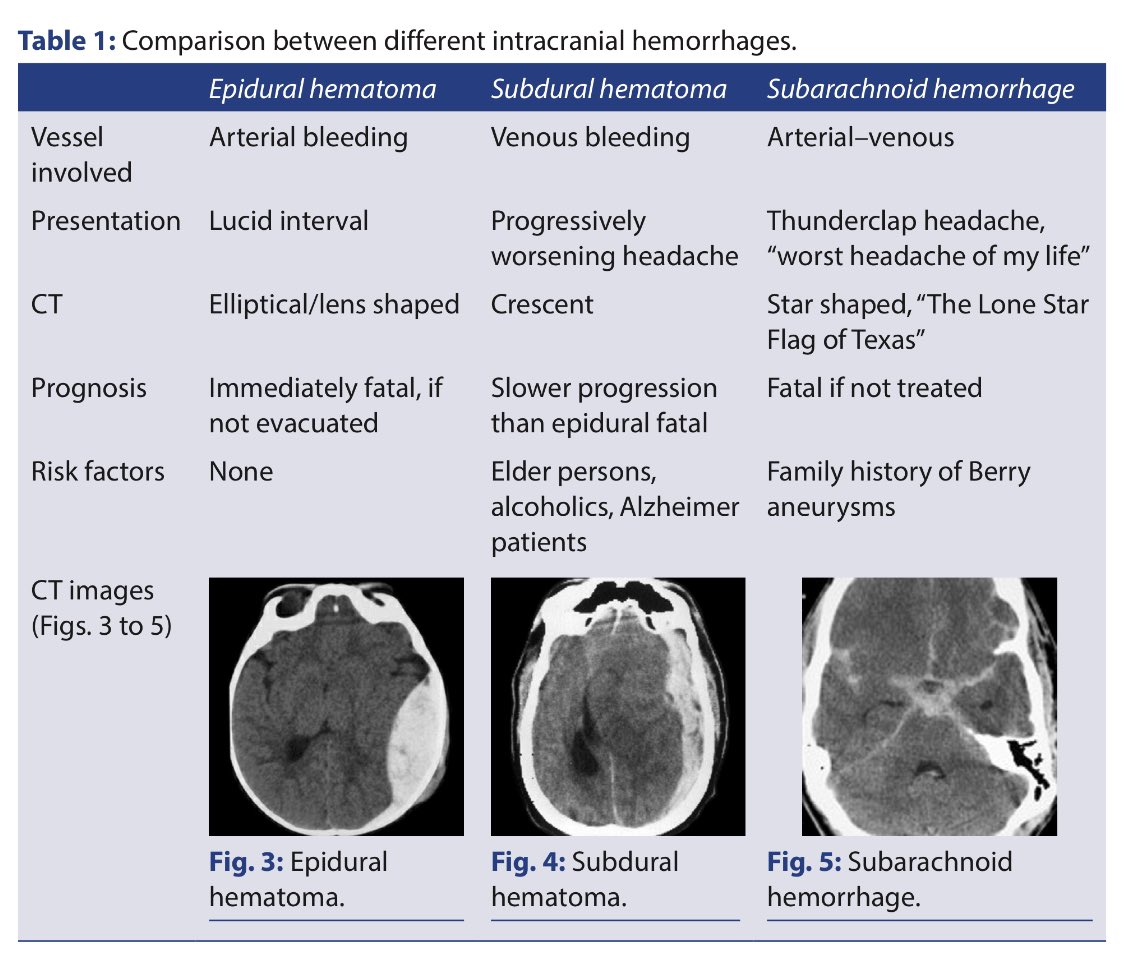

#neurology #ctscan_protocol

-Clinical and radiological features of the stroke syndromes.

-Comparison between different intracranial haemorrhages.

-CT Stroke protocol.

-Time lapse appearence of stroke on CT.